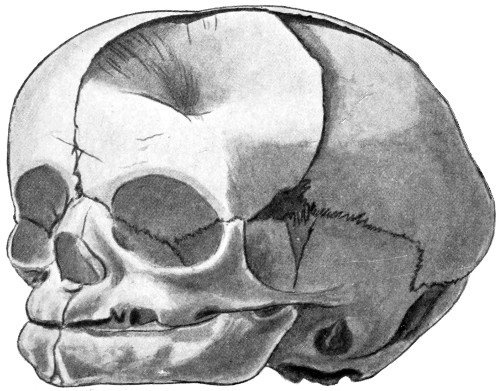

Lyssenkow divided the congenital variety into two main groups—exencephaly and cephalocele—the former resulting from a general error in development (the ‘Acrania’ of Muscatelle), the latter a partial or local developmental failure. In exencephaly there is an extensive gap in the vault of the skull, the remainder of the skull being microcephalic in nature, the brain projecting outwards in a varying degree, and the ventricular spaces distended with fluid. In cephaloceles the hole in the skull is usually circumscribed, although the sutures may be widely separated and the ventricles[32] distended with fluid, yet both skull and brain may be normally developed in all other respects.

The tumour may project through the[33] vault or base of the skull. In the former case, it is almost invariably situated in close relation to the middle line of the skull, from nasion to below the inion.

1. Occipital cephaloceles—the commonest variety—occupy, anatomically, two positions (1) between the two lower segments of the occipital bone (inferior occipital cephaloceles), often involving the foramen magnum and sometimes complicated by a condition of cervical spina bifida, and (2) between the two upper segments of the occipital bone (superior occipital cephaloceles), occasionally involving the posterior fontanelle.

The tumour may possess a broad base or may be definitely pedunculated. In the former instance the gap in the bone may be of considerable size and the margins everted: in the latter case, the hole may be quite small.

The deformity is frequently associated with other congenital defects—hydrocephalus, microcephalus, spina bifida, hare lip, hernia, and talipes.

2. Sincipital cephaloceles occur next in order of frequency. The tumour projects between the nasal bones and the nasal process of the superior maxilla (naso-frontal), between the nasal process of the maxilla and the orbital plates of the ethmoid (naso-ethmoidal), or between the nasal bones (nasal).

3. More rarely, the tumour overlies the anterior or posterior fontanelle. A case of this nature is depicted in Fig. 21, the tumour, situated over the anterior fontanelle, bulging over the temporal and frontal regions to a remarkable extent.

Sincipital cephaloceles are usually quite small, but the occipital variety and those situated in[35] the region of the anterior fontanelle frequently attain a great size (see Figs. 20-22).

The child was 3 months old, and presented a tumour, the size of an orange, situated between the occipital protuberance and the nape of the neck. The mass was pedunculated, the stalk being about the size of a four-shilling piece in diameter. It was soft, translucent, irreducible, and swelled up on coughing. An attempt at removal was carried out, and, after incising the outermost layers, three ounces of cerebro-spinal fluid escaped. A second tumour was then found occupying the base of the swelling. This was also punctured, more fluid escaping. Both sacs were cut away and the wound sewn up. Death occurred on the third day, preceded by convulsions, retraction of the head and neck, and high fever. The autopsy showed that the fontanelles were widely open, the anterior measuring 4 inches from side to side and 21⁄2 from before backwards. The bones of the vault were markedly thinned. In the subdural space there was a quantity of fluid, and the cerebral substance was soft and diffluent, the convolutions flattened, and the ventricles distended. There was a broad gap in the occipital bone, extending downwards into the foramen magnum, and in this situation the cerebellum had bulged backwards into the protruding mass. (See Fig. 22).